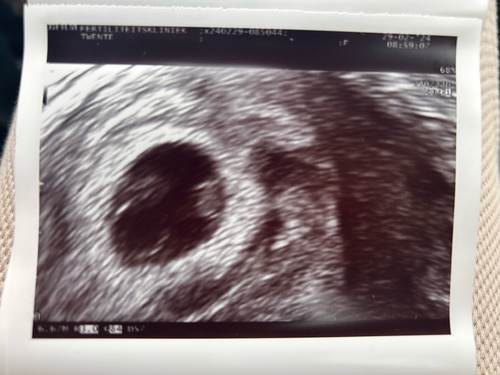

Ik hoop maandag een mooie, duidelijke echo te krijgen! Vandaag waren de beide ukkies (en mijn baarmoeder) dwars en kon de echoscopiste ze er niet mooi opkrijgen.

Bijgevoegde foto is de echo van afgelopen donderdag, met 7+2 weken.